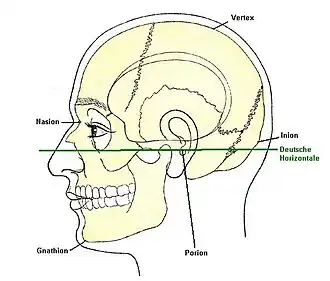

Campersche Ebene (orange Linie)

Campersche Ebene (orange Linie) -

Frankfurter Horizontale (grüne Linie)

Frankfurter Horizontale (grüne Linie) -